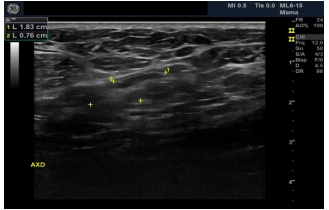

Female patient, black, 76 years old, G3P3, complaining of a lump in the right breast that had appeared 8 months ago. He has a history of admission to the intensive care unit 10 months ago due to an ischemic stroke, presenting left hemiparesis. Presents hypertension, hypothyroidism and dyslipidemia. Family history of father with prostate cancer. He presents sclerocalcification in the mitral and aortic valve on the echocardiogram. He presented clinical signs of an initial dementia process.Ultrasonography showed a heterogeneous image of 3.9/2.4/3.7cm in the union of the upper quadrants of the right breast, axillary lymph nodes with proportionality between cortex and hilum bilaterally BI-RADS 4 B BI-RADS 4 B.

On palpation, there was an 8cm nodule in the right breast and mobile and fibroelastic axillary lymph nodes. There were no palpable nodules in the cervical or supraclavicular region bilaterally. A core needle biopsy was performed with an anatomopathological result of triple-negative grade 2 adenoid cystic carcinoma. Staging demonstrated two 1.1cm pulmonary nodules with soft tissue density suggesting metastasis. Abdominal tomography demonstrated liver nodules suggestive of secondary implants. The PET scan confirmed uptake in the lung and liver nodules, in addition to lytic lesions in S3. Liver biopsy confirmed implantation of adenoid cystic carcinoma. The patient was staged as T2N0M1. Chemotherapy was started with a regimen of Carboplatin, Paclitaxel and Pembrolizumab. After the third cycle of chemotherapy, the breast was reevaluated without showing any tumor reduction. The metastases also did not regress, and treatment was interrupted. The patient evaded the service until he returned in January 2024 complaining of pain in his right hip and difficulty walking. Chest and hip tomography showed an increase in lung lesions and the appearance of lytic metastasis in the iliac bone (figure 1, 2, 3).

Our patient died within 1 year after diagnosis, in line with reports of survival in 5, 10 and 15 years of 98.1%, 94.1% and 91.4%, respectively [3,16,17]. The literature describes stability of tumor size for 1 to 2 years, corroborating our case in which the tumor was practically stable during 1 year of follow-up [13]. There are cases in the literature of slow tumor growth over a period of 9 years in a patient who denied treatment [13]. A. heterogeneous image presentation on ultrasound is compatible with the aspect described in the literature [13].